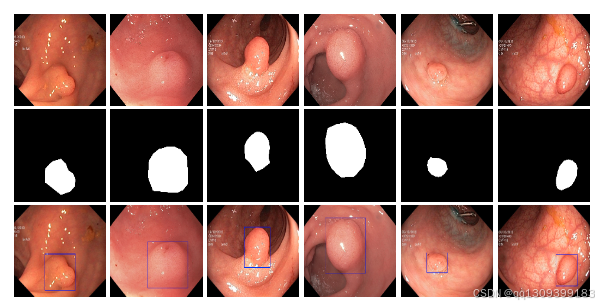

在这里插入图片描述

本工具基于Kvasir-SEG数据集开发(该开源数据集包含胃肠道息肉图像及对应分割掩模,由经验丰富的胃肠病专家手动标注并验证),采用基于U-Net架构的深度学习模型,可自动从结肠镜图像中分割息肉,为医疗专业人员提供辅助诊断工具。生成的视觉分割掩模有助于优化初步诊断流程并支持治疗规划。